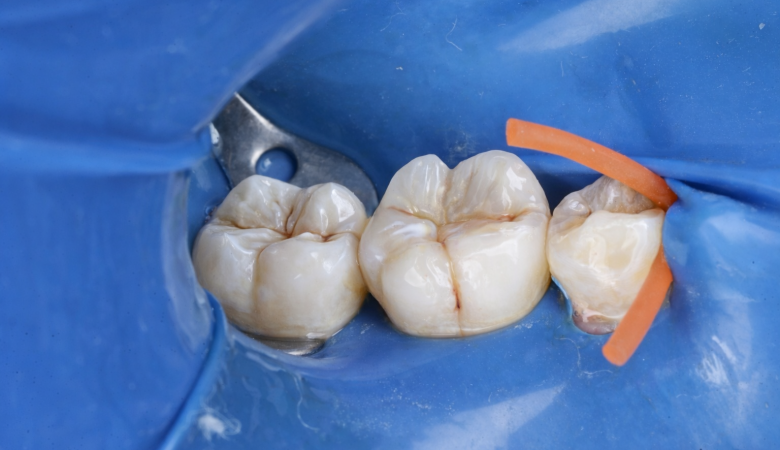

Brand: GC ,Tukoyama

Material: Ever x .posterior from gc, Tokoyama

Technique: Class 2 Build Up, DME on 2 steps

Class II Deep Margin Elevation Following Single-Visit Endodontic Treatment Under Strict Isolation Adhesive-Driven Rehabilitation of a Mandibular First Molar Author: Dr. Hamza Zahid Microscopic Restorative Dentist Abstract Deep proximal caries extending subgingivally present both biological and restorative challenges. When combined…